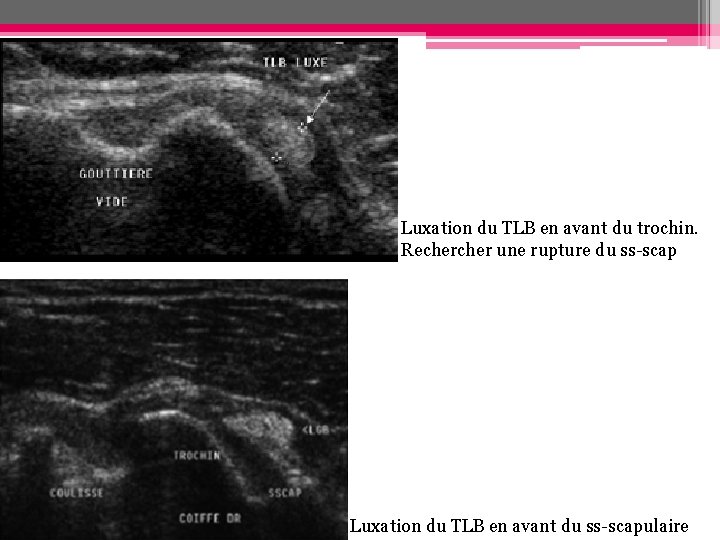

• On distingue: - Les luxations intra-articulaires - Les luxations en avt du trochin ou dans le ss-scap (Les luxations en avt du ss-scap intact (très rares/ruptures traumatiques sévères du sus ou ssépineux) Subluxation du tendon sur toute la hauteur de la gouttière bicicpitale A. Luxation intra-articulaire avec désinsertion du ss-scap B. Luxation intraarticulaire avec rupture profonde du ss-scap C. Luxation en avant du trochin ou ds le ss-scap D. Luxation en avt du ss-scap intact

Luxation du TLB en avant du trochin. Recher une rupture du ss-scap Luxation du TLB en avant du ss-scapulaire